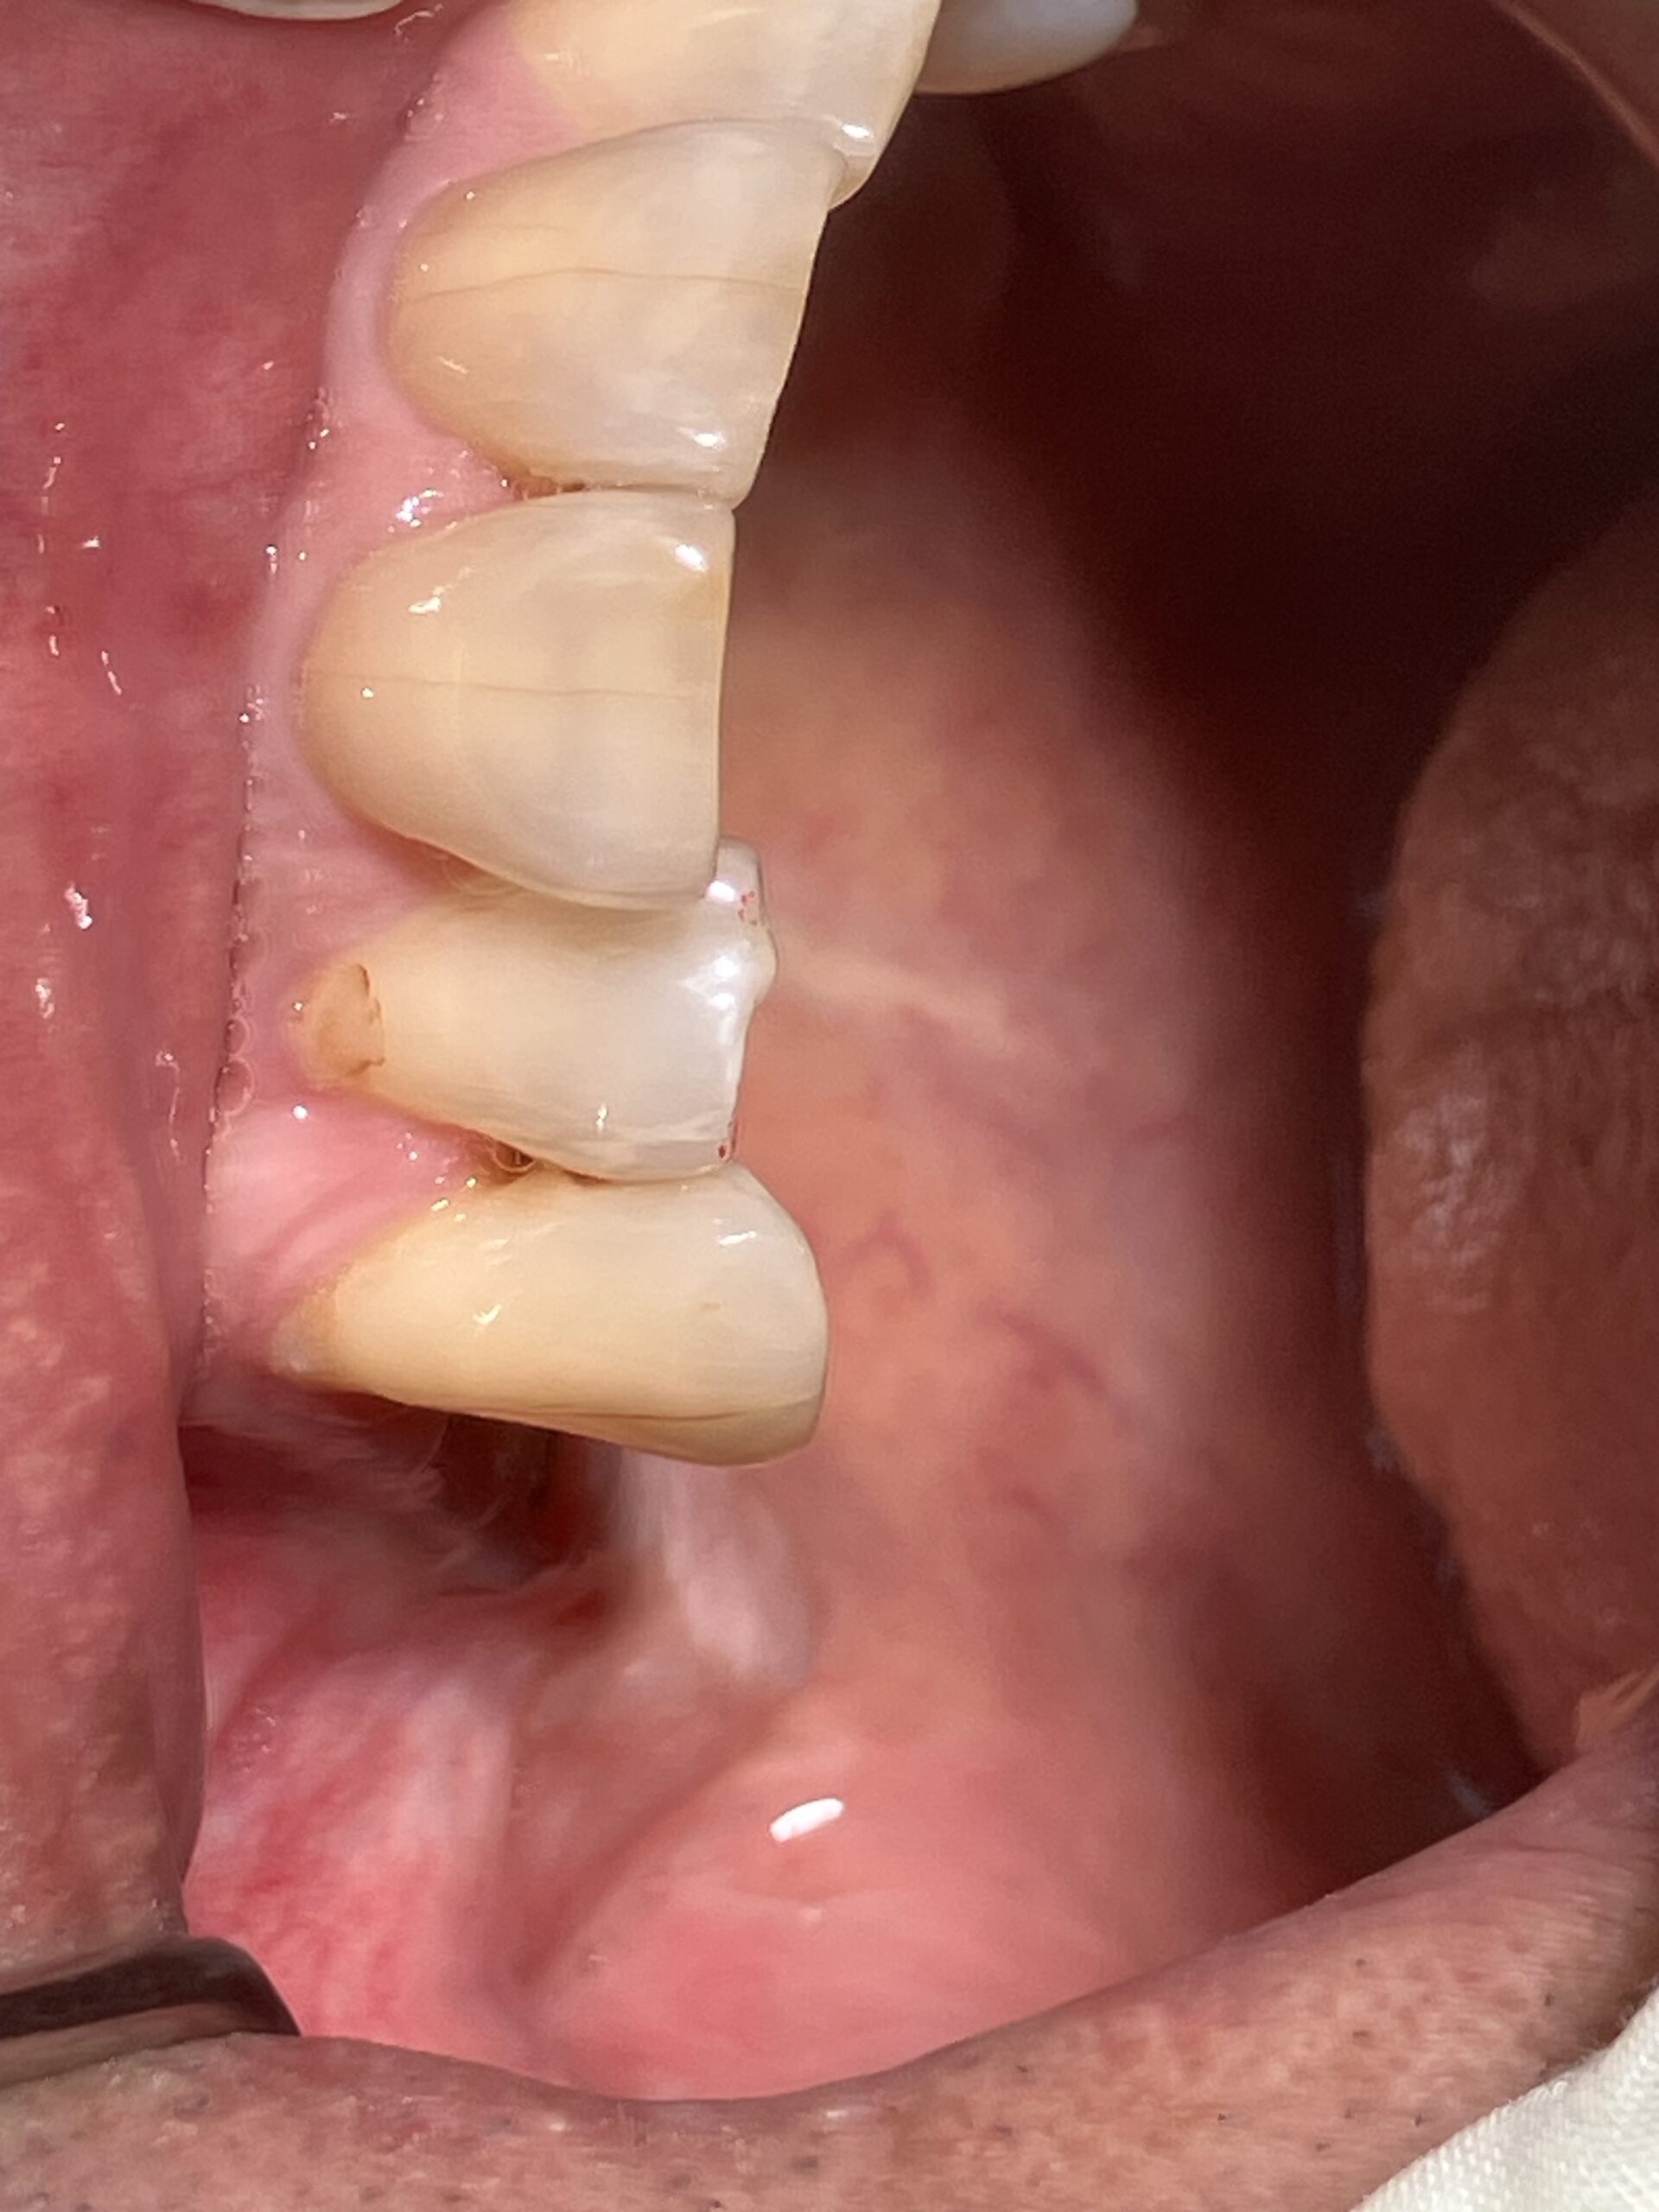

- 自然な見た目: 近年、審美性の高いジルコニア素材が登場しており、天然歯に近い色調や透明感を再現できます。金属を使用しないため、歯茎の変色(メタルタトゥー)の心配もありません。

- プラークが付着しにくい: 表面が滑らかなため、 歯石やプラークが付着しにくく、 インプラント周囲炎のリスクを低減する可能性があります。